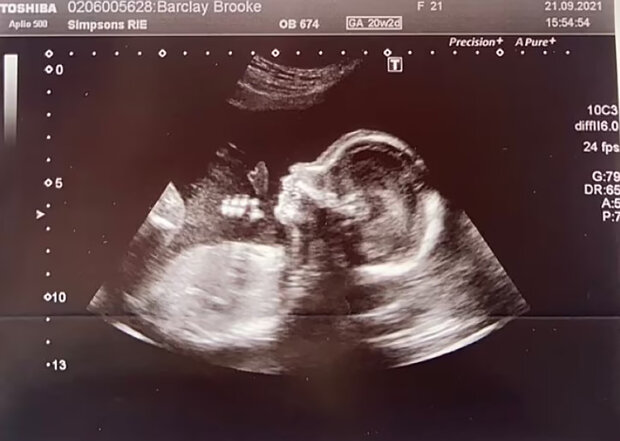

Když si žena uvědomila, že je v jiném stavu, všimla si, že postupem času jí neroste bříško.

Brooke také sdílela, že těhotenství jí nepřináší žádné problémy. Podstoupila vyšetření, během kterého se ukázalo, že nemá žádné zdravotní odchylky. Plod se vyvíjí normálně.

"Upozornila jsem, že břicho se velmi pomalu zaokrouhluje. Všechno je tak vážné, že nikdo kolem mě nevěří, že nosím dítě," svěřila se Brooke.